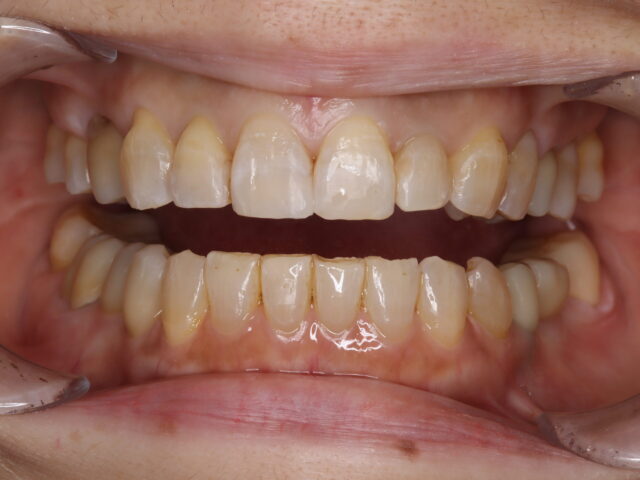

術後口腔内

綺麗な歯並びとなっている

補綴やりかえも行なったことで審美的に大きく改善している